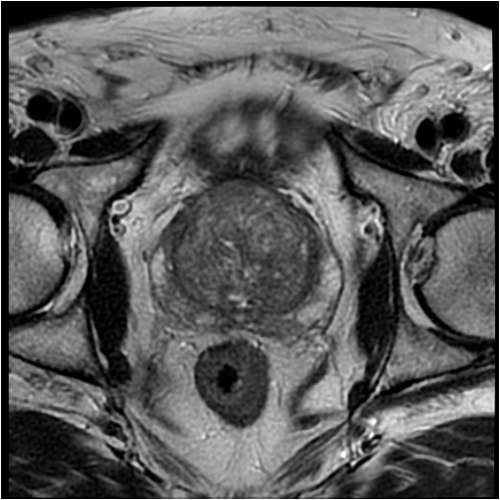

Focal therapy for prostate cancer – ready for prime time?

The current therapeutic ratio for radical therapy in many men with localised prostate cancer is not ideal. For a significant side-effect profile, there seems to be a small survival benefit over a 10-15 year period. A strategy that might balance...